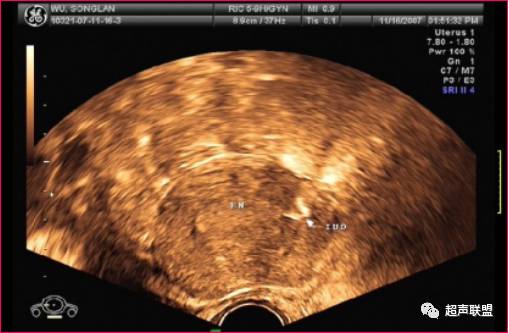

节育器嵌顿

节育环(IUD)嵌入子宫肌层内.

(经阴道超声)

1、节育环嵌顿

正常时子宫显示良好,宫腔内膜平滑可见,IUDIUD嵌顿时显示IUD上缘与宫底浆膜层之间的距离小于1.0cmIUD至子宫前后壁浆膜层距离不对称,IUD强回声平面与宫腔平面不平行,发生了角度的变化,或IUD某一部分突向子宫壁。剖宫产子宫下段横切口肌层愈合不良时,IUD尤其是TIUD纵臂下端易嵌入切口处,或完全置于浆膜下。节育器嵌顿可与节育器的大小、形状、质地及术者操作技术有关。